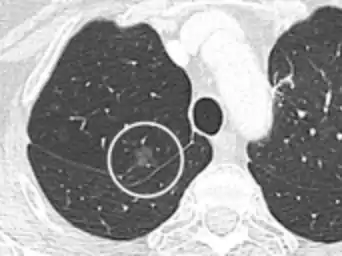

Spiculated lung nodule.[9]

- Margin morphology: a spiculated margin is a risk factor for cancer.[8] Benign causes tend to have a well defined border, whereas lobulated lesions or those with an irregular margin extending into the neighbouring tissue tend to be malignant.[10] In particular, spiculations are highly predictive of malignancy with a positive predictive value up to 90%.[9] Also, a "notch sign", which is an abrupt indentation of the nodule, increases the risk of cancer, but may also be found in granulomatous diseases.[9]